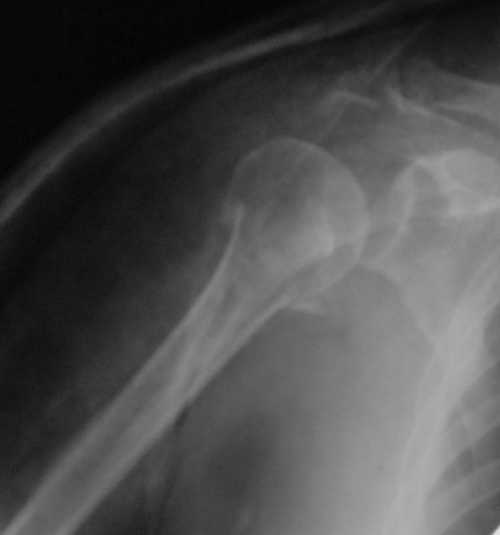

Снимки на 1-е сутки после репозиции и на 8- сутки после репозиции.

Пожалуйста

С ув. Sergey A. Melashenko, г. Запорожье

Никто не отменял функционального консервативного метода лечения. Дело не только в том, что перелом сросся, вопрос в каком положении.

При переломах хирургической шейки плеча ротаторная манжетка ротирует фрагмент головки внутрь, поэтому при неустраненном упомянутом смещении

перелом рано или поздно срастется, но отведение плеча будет страдать. Очень практичен и функционален метод А.Ф. Лазарева, о котором упомянул Джолдас, ранее обсуждался на форуме , попробуйте, больные будут довольны